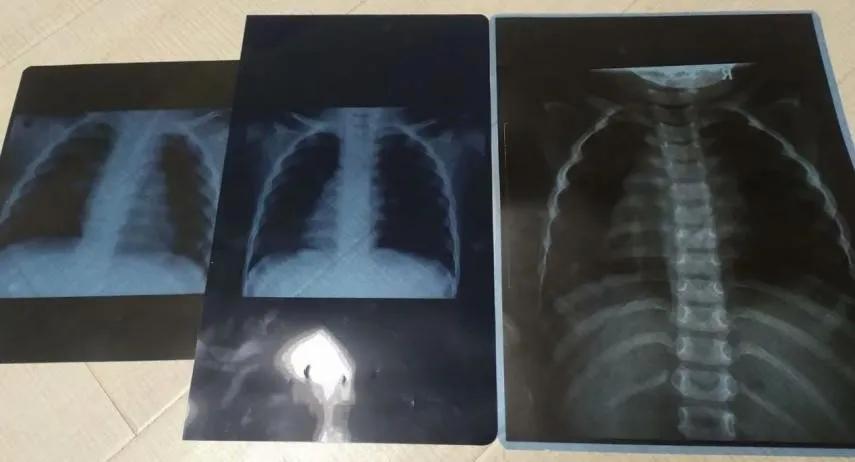

这是我2次肺炎+1次支气管炎的胸片